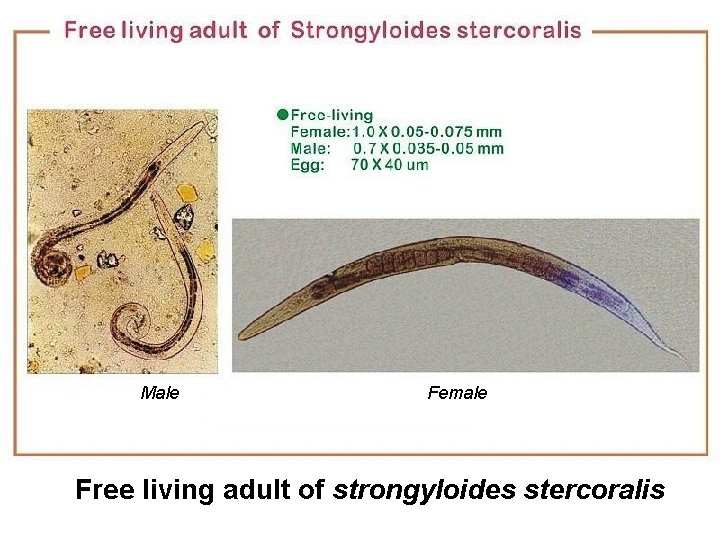

Male Female Free living adult of strongyloides stercoralis